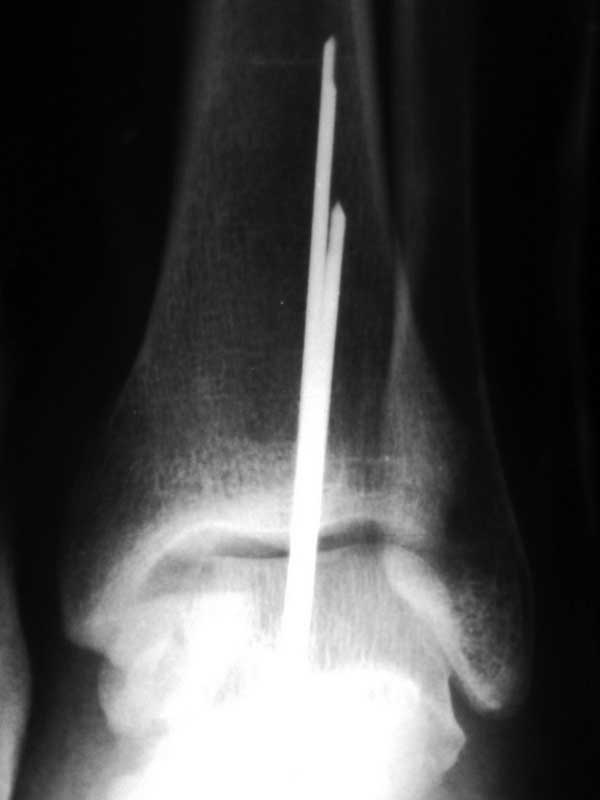

Вчера сделали повторную репозицию и фиксацию спицами. Сейчас будут снимки)))

Metalurg 27 Январь 2012, 12:49

Прямая проекция